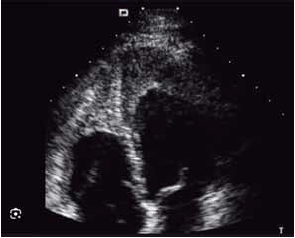

Paciente com dispneia aos esforços realiza o ecocardiograma a seguir.

(Arquivo pessoal; imagem usada com autorização)

A imagem sugere qual causa de miocardiopatia restritiva?